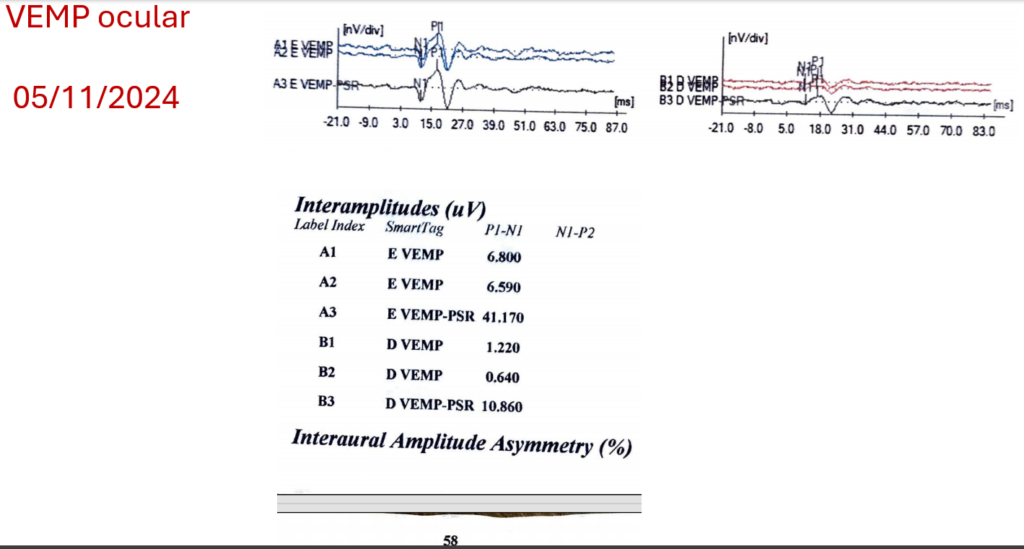

O VEMP cervical mostrou que com a retificação eletromiografica não há diferença de amplitude P1-N1 entre os lados. Resposta sacular simétrica.

Já no VEMP ocular, o índice de assimetria interaural da amplitude N1-P1 está alterado, indicando que há dano a função utricular direita.